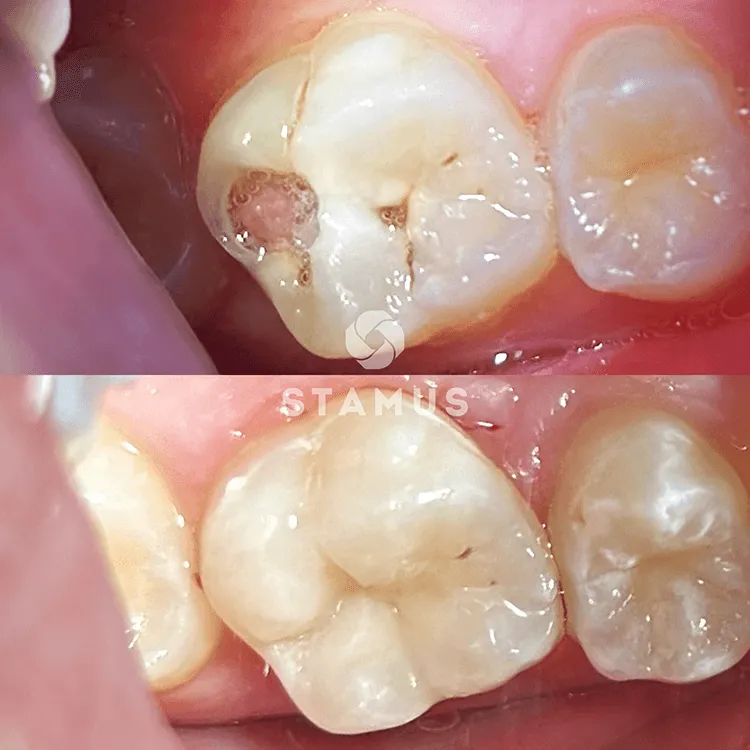

Пациентка пришла на прием с целью санации полости рта

Пациентка обратилась с целью санации полости рта. Зуб ранее был лечен

Была проведена очистка поверхности зуба от налета, анестезия и изоляция рабочего поля системой Коффердам, снятие старой пломбы, препарирование и фторирование полости. Произведена постановка пломбы фирмы Harmonize, шлифование и полирование пломбы